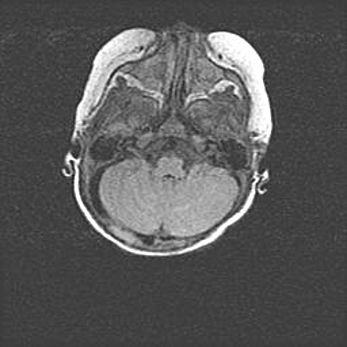

Церебральная ишемия II.

Возраст: 5 дней

Вес: 3400 г

Пол: женский

Окружность головы: 35 см

Срок гестации: 39 недель

Церебральная ишемия – это заболевание, характеризующееся недостаточностью (гипоксией) либо полным прекращением (аноксией) снабжения мозга кислородом по причине закупорки одного или нескольких сосудов. Это приводит к  что метаболическим расстройствам различной степени тяжести в тканях головного мозга, развитию коагуляционных некрозов и гибели нейронов.